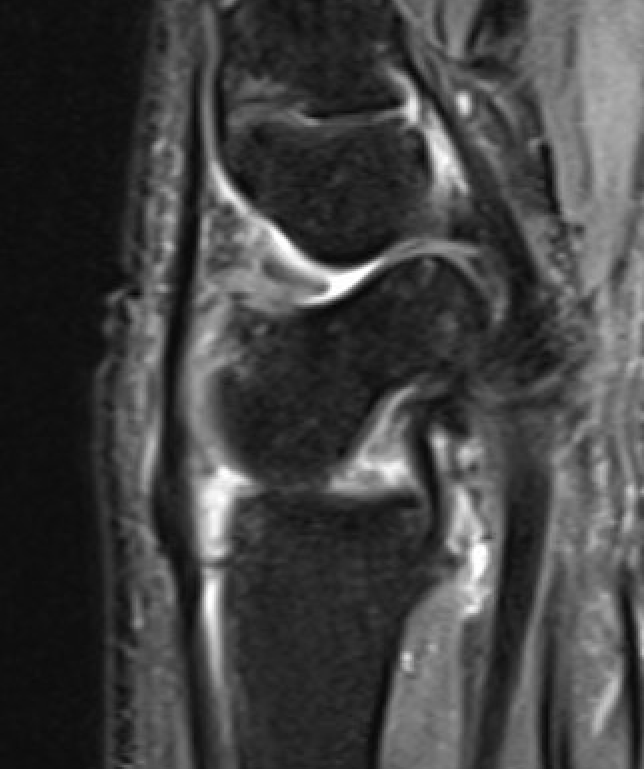

MRI

SL ligament injury with minimal disassociation / SL separation / dynamic instability

SL ligament injury with SL separation and static instability

Increased scapholunate angle